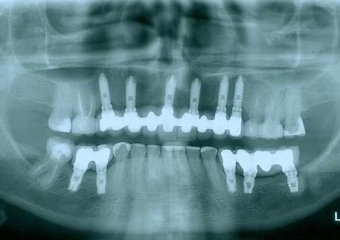

Rx Final